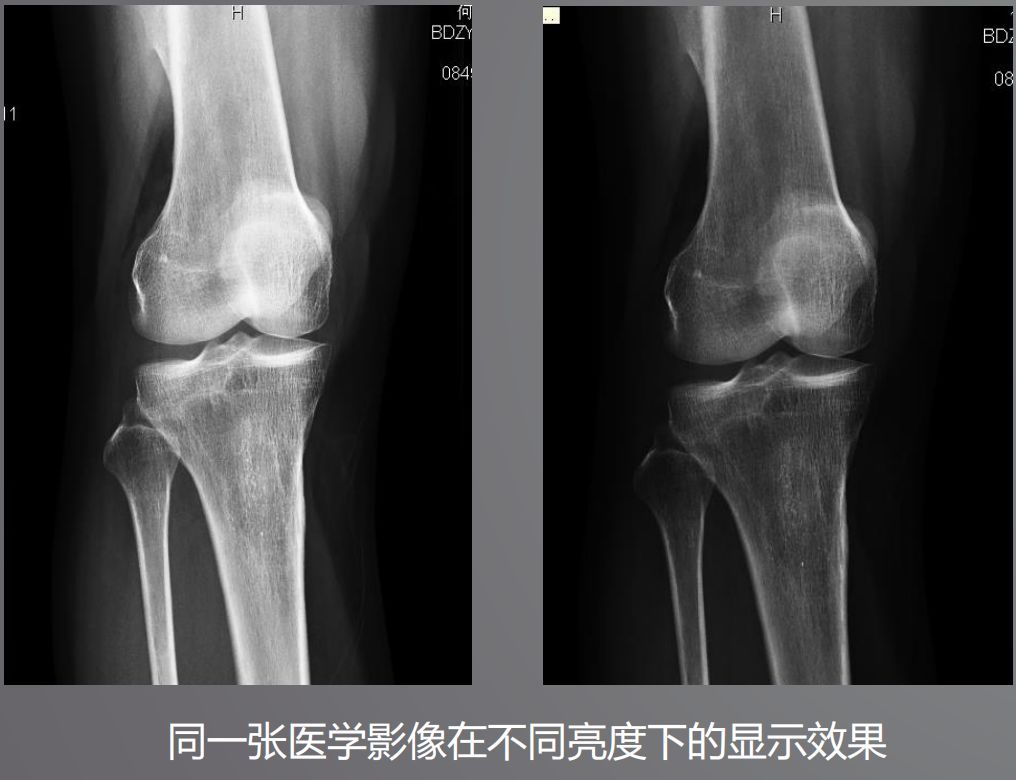

三、高亮度

高亮度從字面上就非常好理解了,回想在傳統(tǒng)膠片時代,閱片都是直接夾在大大的發(fā)光白板上。而平時我們?yōu)g覽網(wǎng)頁或者看視頻并不需要那么高的亮度,導(dǎo)致普通顯示器亮度偏低,達不到醫(yī)用閱片的標準。

根據(jù)DICOM Part14規(guī)定,所有醫(yī)學顯示器必須符合GSDF的標準,確保顯示區(qū)域亮度符合一致性。而普通顯示器是不需要刻意符合這個標準的。

醫(yī)用顯示器通過系統(tǒng)測量和調(diào)整每一個像素的亮度,降低中心和角落之間亮度和色彩的不均勻性,通過減少這些差異,確保顯示器每個顯示區(qū)都能符合DICOM GSDF標準。